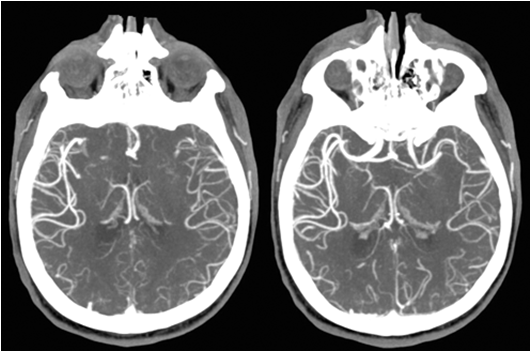

7) CT angiography

aneurysm, stenosis, dissection, AVM 진단을 위해 촬영한다.

https://www.ucsfhealth.org/medical-tests/ct-angiography---head-and-neck

CT angiography - head and neck

CT angiography (CTA) combines a CT scan with the injection of dye. CT stands for computed tomography. This technique is able to create pictures blood vessels.